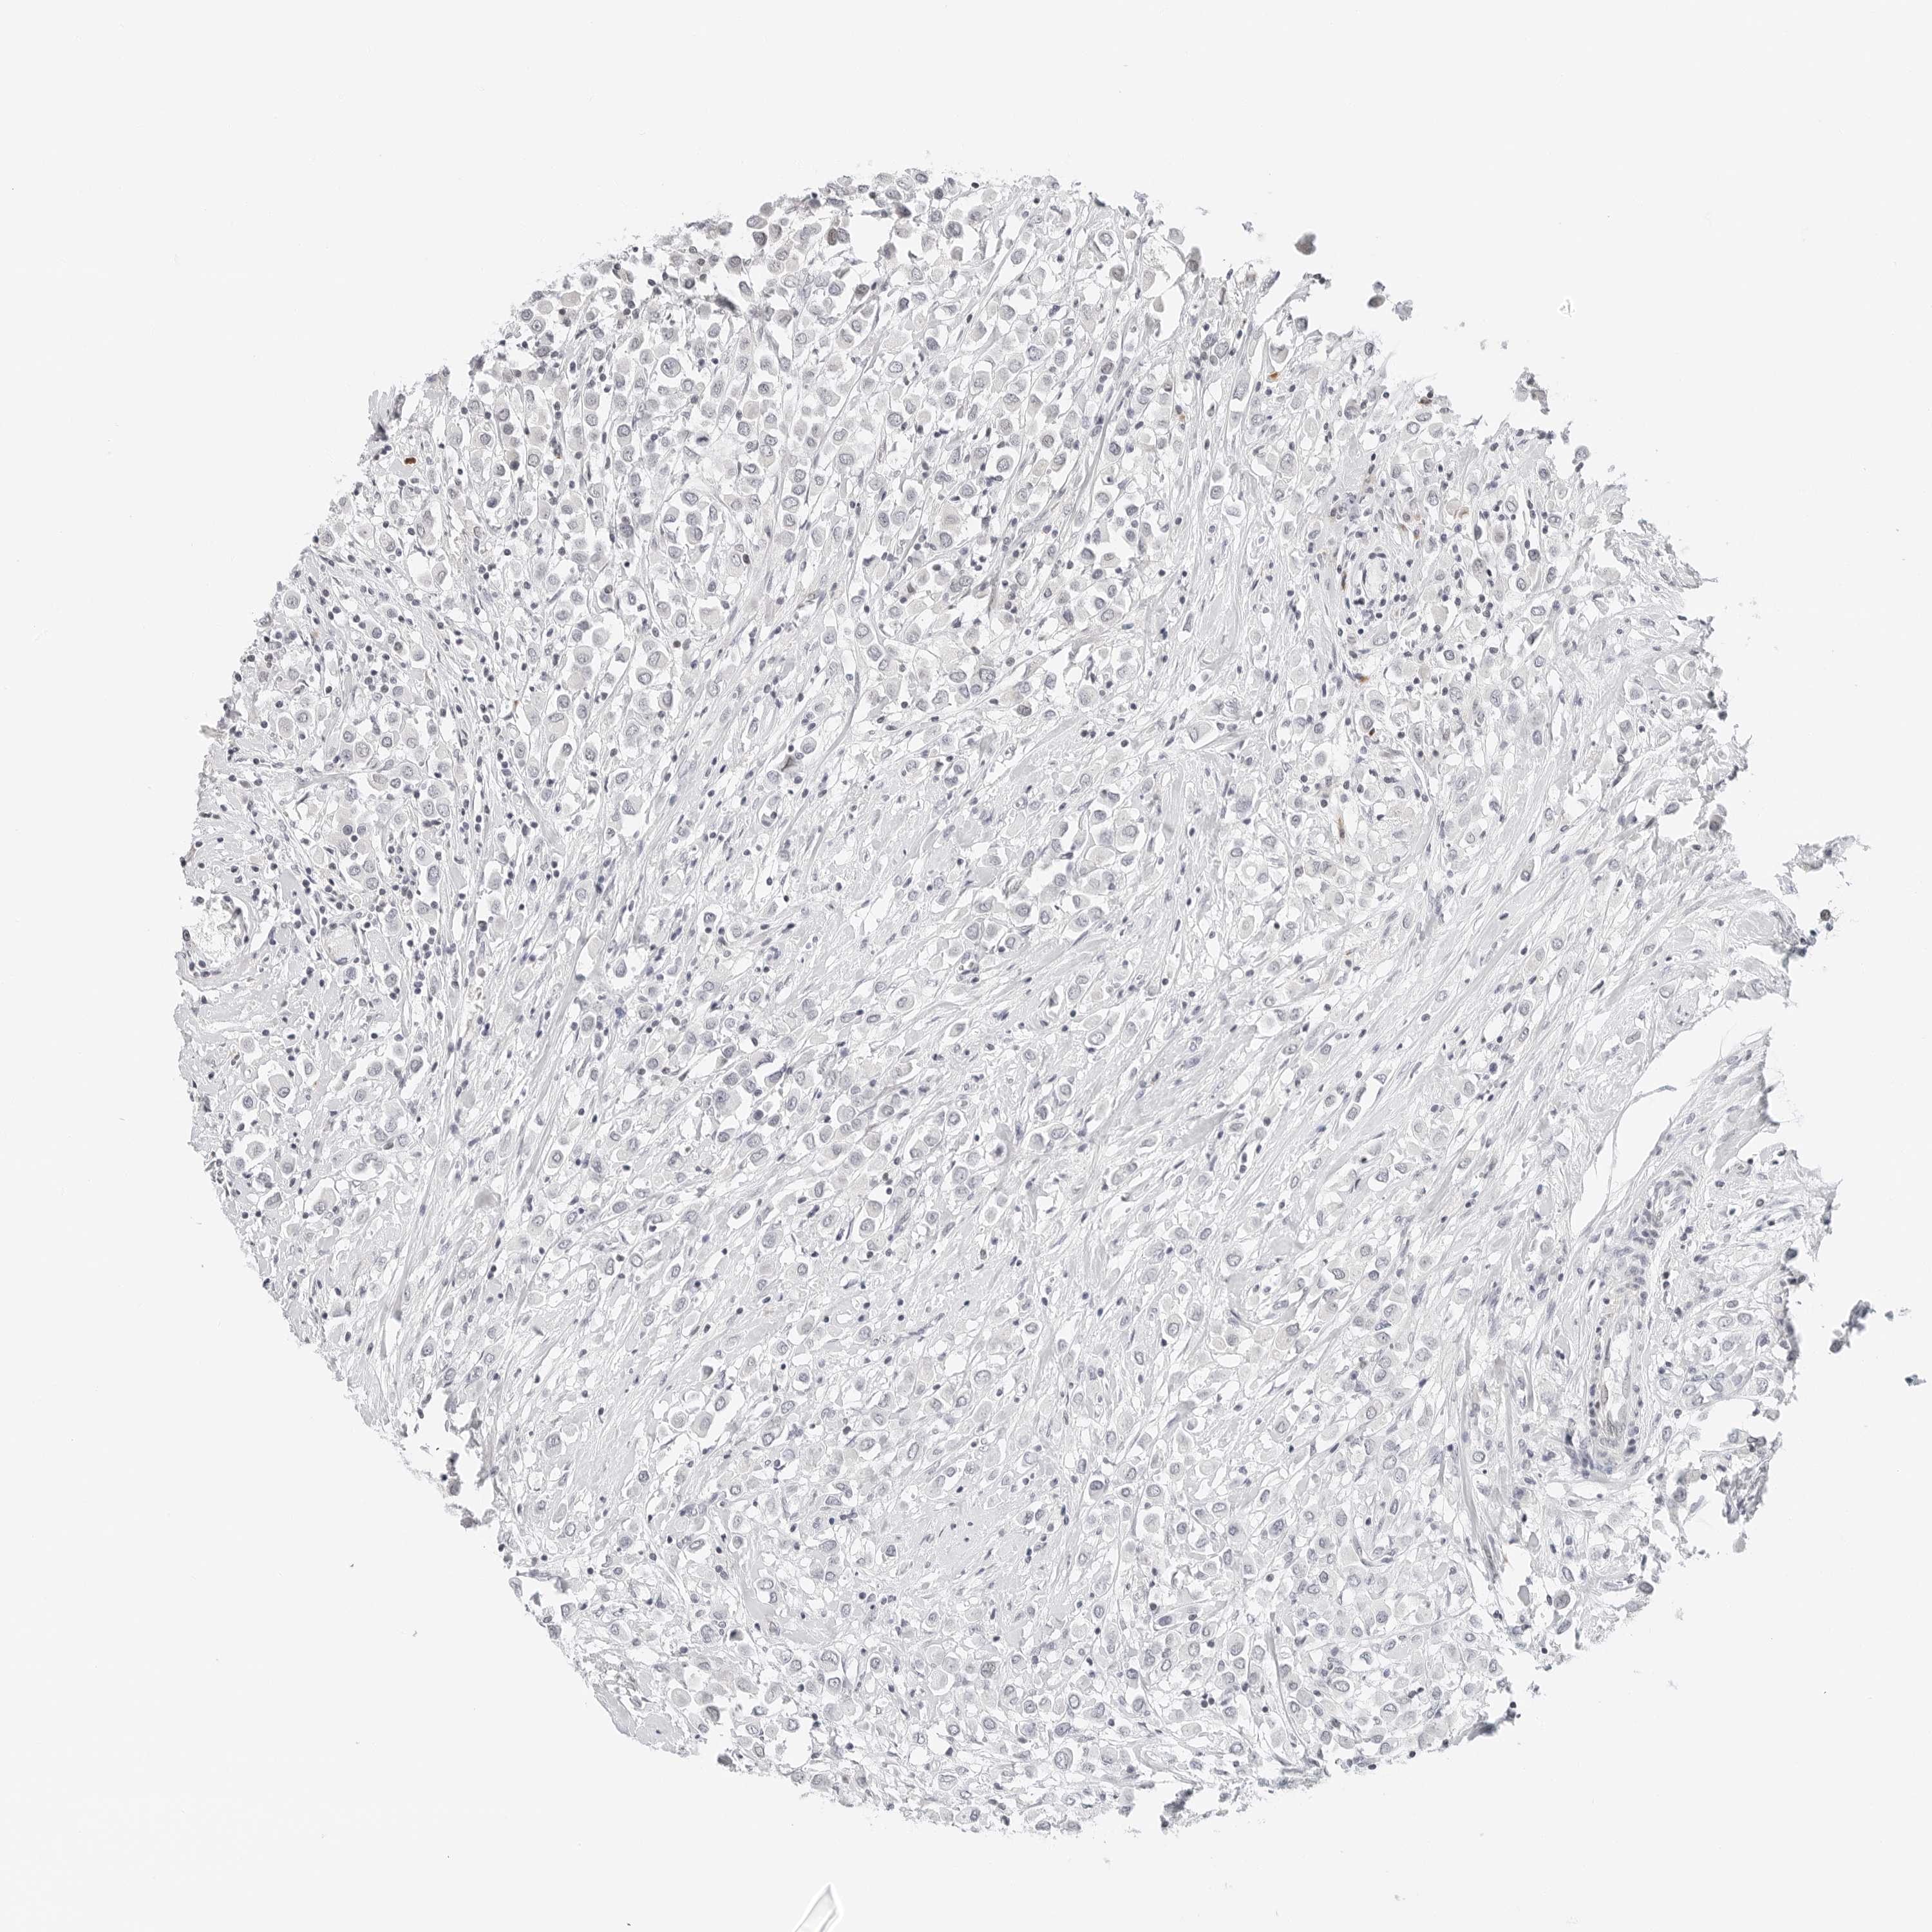

CANCER BREAST CANCER Show tissue menu

BRCA TCGA BRCA VALIDATION PROTEIN EXPRESSION